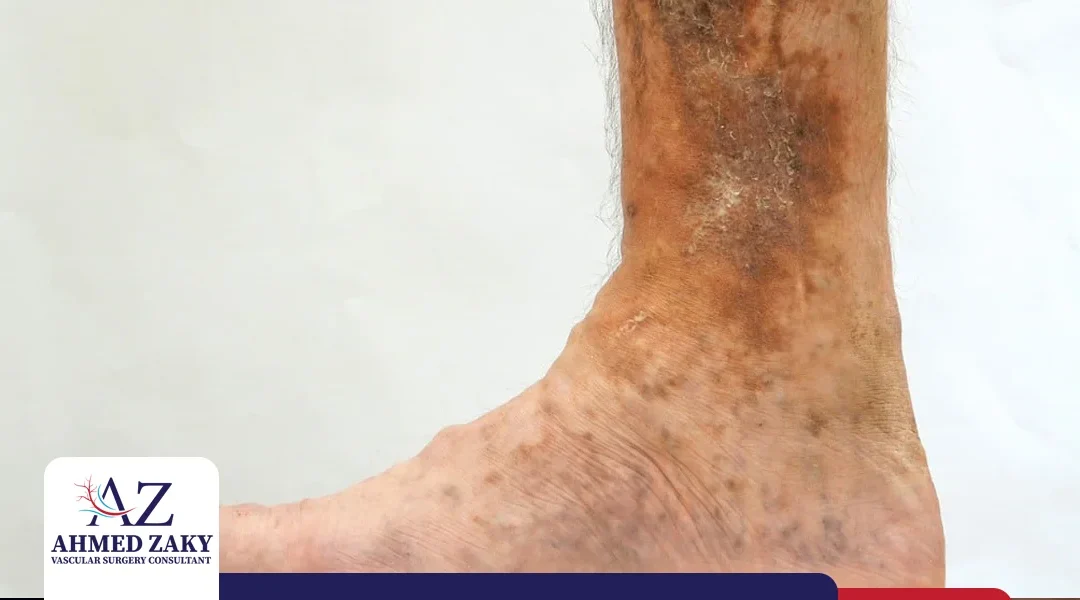

قرحة الساق الوريدية هي عبارة عن جروح غير ملتئمة تظهر عادة في الثلث الأخير من الساق فوق الكاحل من الداخل. تختلف أساليب علاج قرحة الساق الوريدية عن علاج الجروح التقليدية، وذلك لأنها تنشأ بسبب ارتفاع ضغط الدم الوريدي. وفي هذا المقال، يوضّح لنا الدكتور أحمد زكي -مدرس...